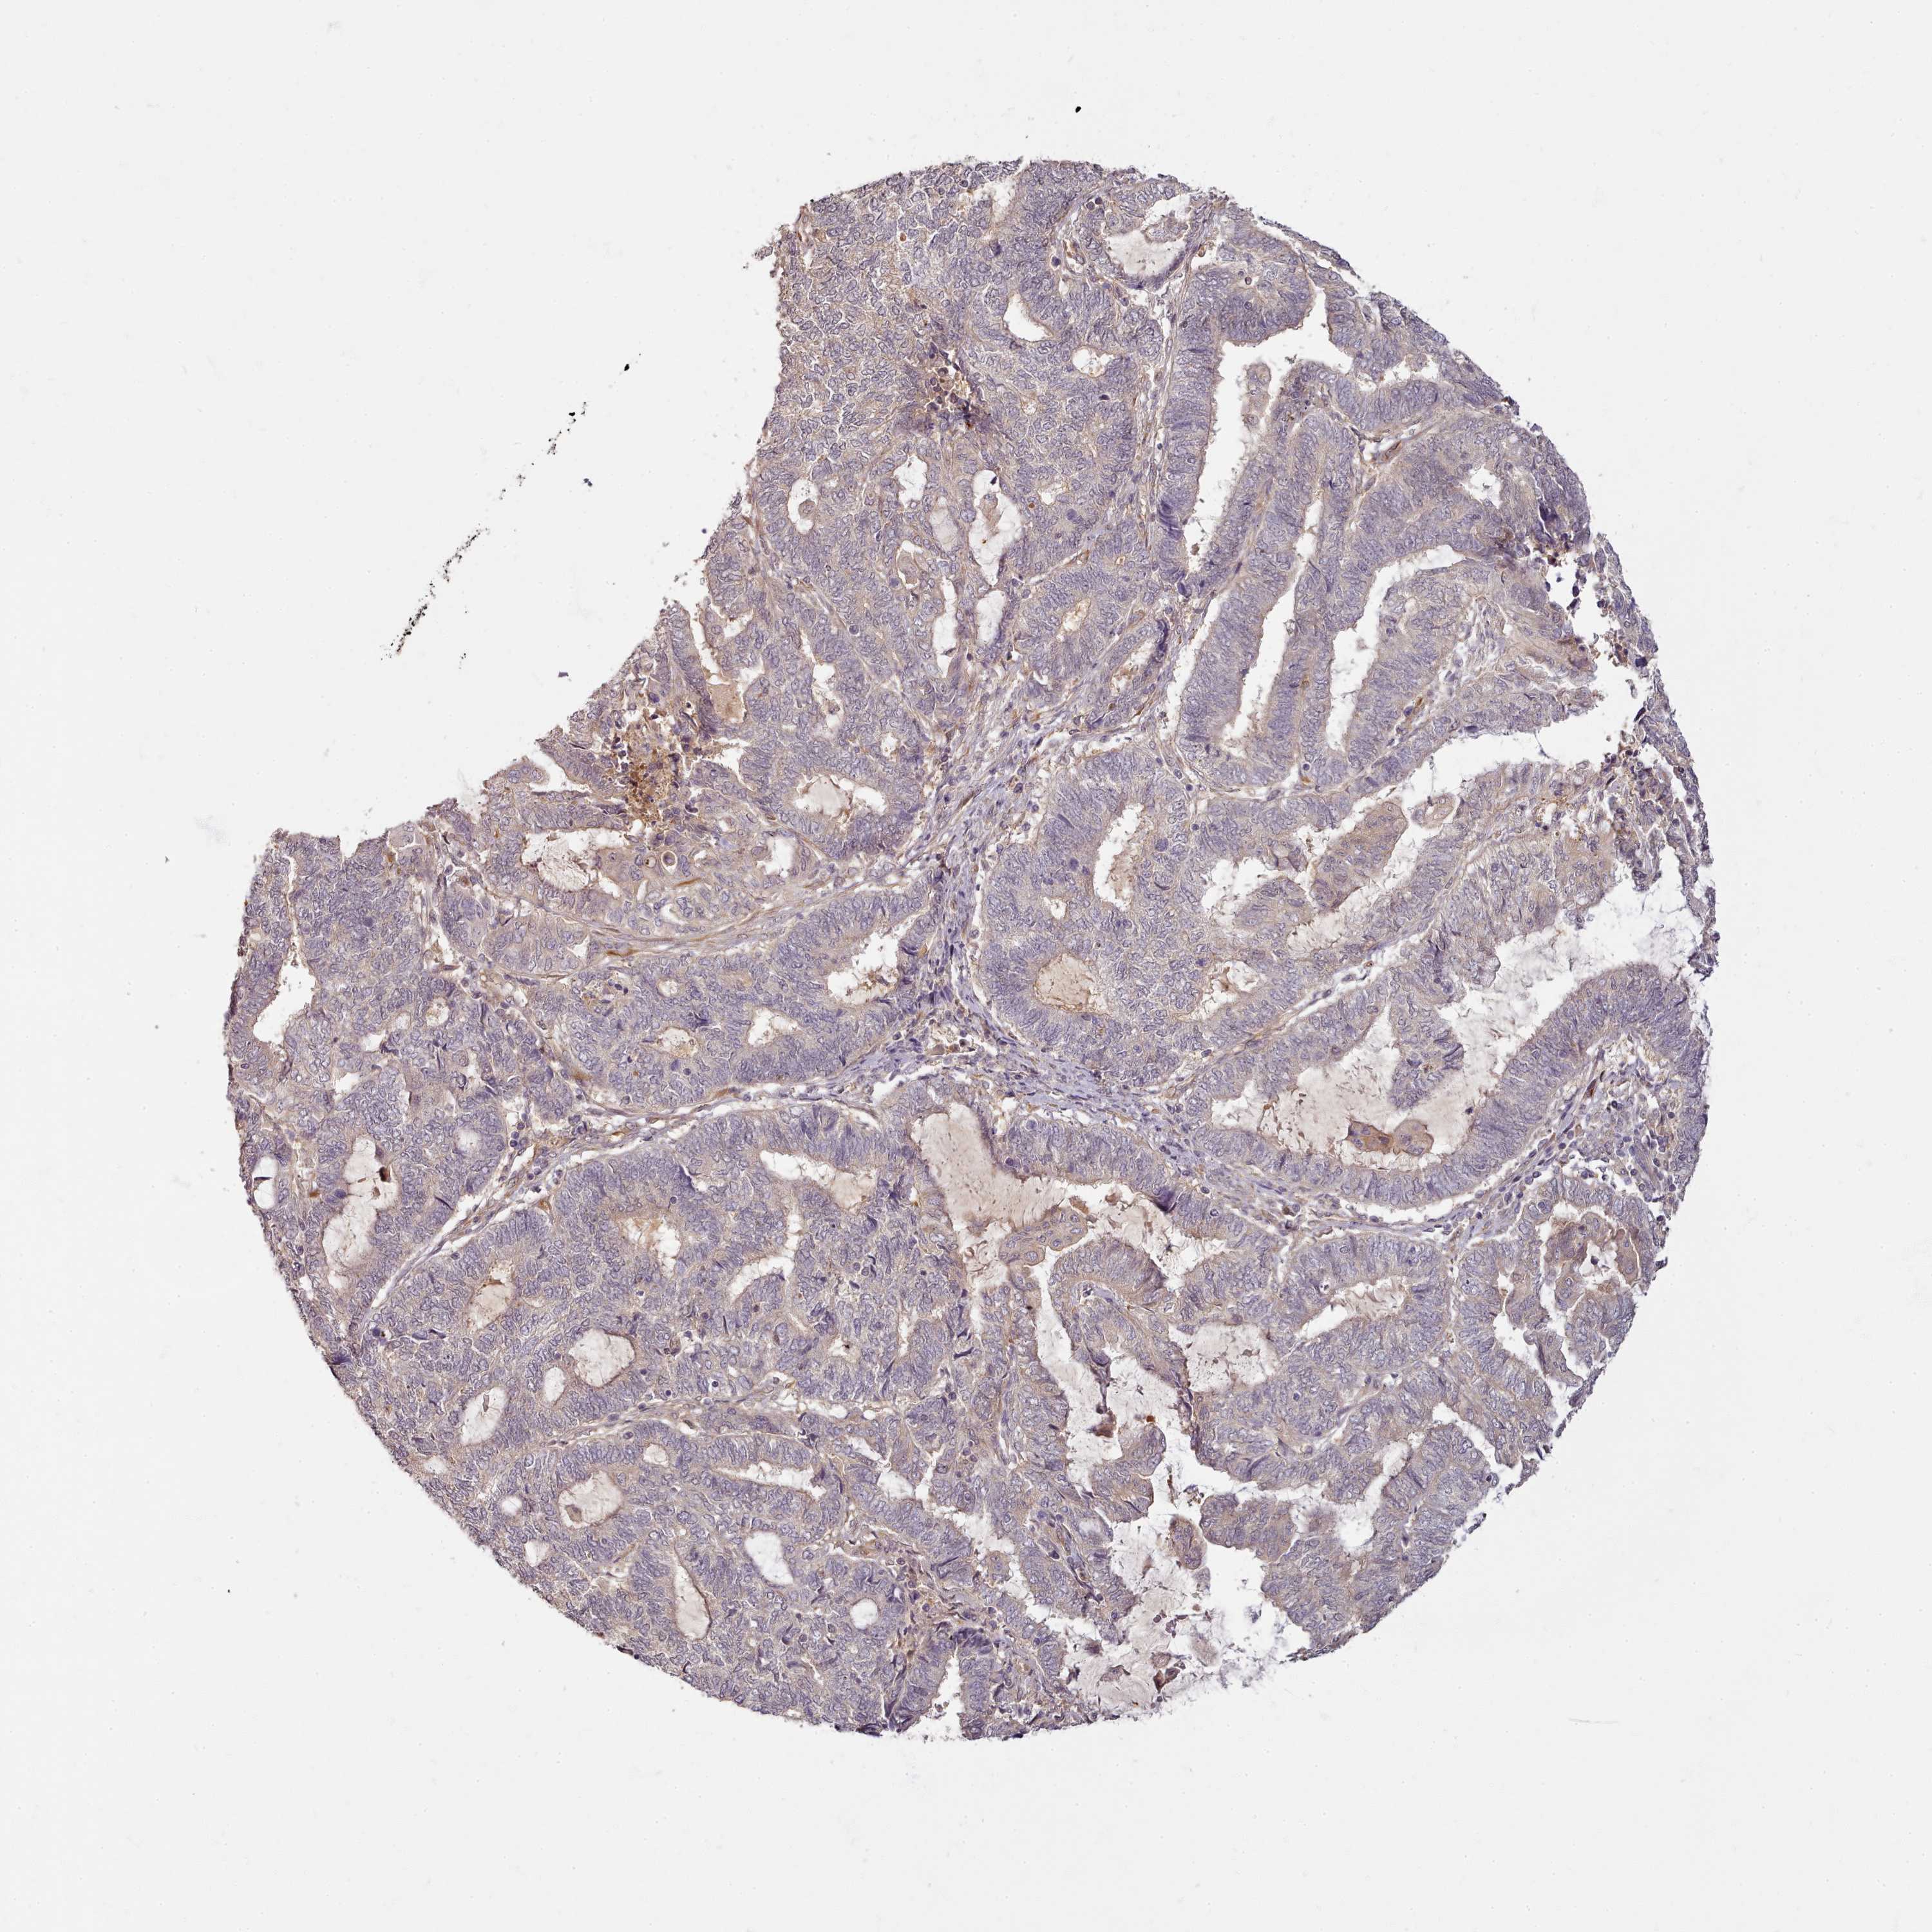

ENDOMETRIAL CANCER - Protein expressioni

A mouse-over function shows sample information and annotation data. Click on an image to view it in a full screen mode. Samples can be filtered based on level of antibody staining by selecting one or several of the following categories: high, medium, low and not detected. The assay and annotation is described here.

Note that samples used for immunohistochemistry by the Human Protein Atlas do not correspond to samples in the TCGA dataset.

Antibody stainingi

Antibody staining in the annotated cell types in the current human tissue is reported as not detected, low, medium, or high, based on conventional immunohistochemistry profiling in selected tissues. This score is based on the combination of the staining intensity and fraction of stained cells.

Each image is clickable and will lead to virtual microscopy that enables deeper exploration of all samples and also displays staining intensity scores, fraction scores and subcellular localization as well as patient and tissue information for each sample.

Antibody HPA038604

Antibody CAB025607

Staining

High

Medium

Low

Not detected

Intensity

Strong

Moderate

Weak

Negative

Quantity

>75%

75%-25%

<25%

None

Location

Nuclear

Cytoplasmic/membranous

Cytoplasmic/membranous,nuclear

Adenocarcinoma, NOS